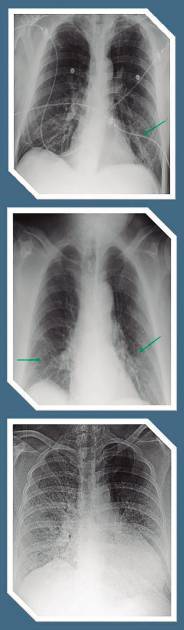

En el caso de las enfermedades respiratorias, la información disponible indica que también las personas asintomáticas, las que no tienen o tuvieron síntomas muy graves y aquellas que no fueron hospitalizadas presentan porcentajes de fibrosis en los pulmones.

“Eso definitivamente deja un órgano disfuncional y muchas personas han tenido que reaprender a respirar para aprovechar ese 50 por ciento de pulmón que les queda. Eso es una condición incapacitante”.